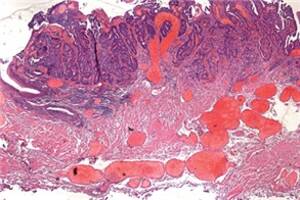

In einem begleitenden Editorial in den »Annals« erklärt Professor Dr. Sharon Lewin von der australischen Monash University, warum die Suche nach einer Heilung von HIV so kompliziert ist (doi: 10.7326/M14-1573). Eine ART könne HIV-Infizierte nicht heilen, weil sie latent infizierte, ruhende T-Zellen nicht erreiche, die lange Zeit persistierten. Diese Zellen weisen in ihr Genom integrierte Virus-DNA auf, teilen sich aber nicht. Sie bilden sich rasch nach der Infektion, reichern sich in bestimmten Körper­geweben wie dem Gastrointestinaltrakt an und haben eine extrem lange Halbwertszeit. Daneben scheinen andere langlebige infizierte Zellen wie naive T-Zellen, Astrozyten und Mikroglia eine Rolle zu spielen.